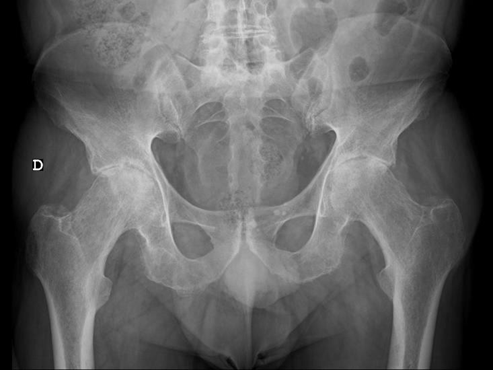

An X-ray of the hip revealed advanced bilateral osteoarthrosis, classifying both hip joints as grade 3 according to Tonnis' classification (Figure 2).

Figure 2 Pre-arthroplasty hip X-ray.

Upon reassessment one month after the surgery, the pain in the left hip had subsided, and he was not taking analgesics. He walked with the support of two crutches because of pain in the right hip, which became more evident after the left hip arthroplasty. He performed 90º of active flexion of the left hip and managed 20º of passive internal and external rotations of the hip pain-free. No signs of hip prosthesis loosening were found in the control radiographic study (Figure 6).

Figure 6 Post-arthroplasty hip X-ray.